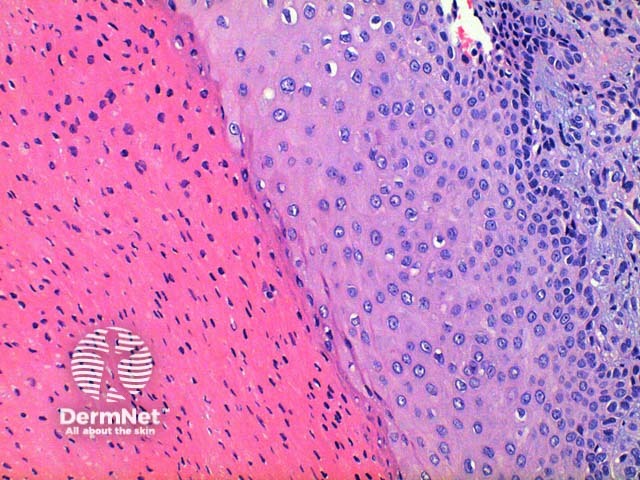

Scanning power view of trichilemmal cyst shows a epithelial lined cyst filled with brightly eosinophilic keratinaceous debris (Figure 1). Focal rupture of the cyst may occur with an associated giant cell reaction (Figure 2). Closer inspection of the cyst wall identifies trichilemmal differentiation (Figures 3 and 4) as occurs in the outer root sheath of the hair follicle. This is seen as maturation of squamous epithelium with lack of a granular layer. The eosinophilic keratin centrally is densely packed frequently displaying cholesterol clefts. Focal calcification is seen in around 25% of cases (Figure 5).

Figure 3

Figure 4